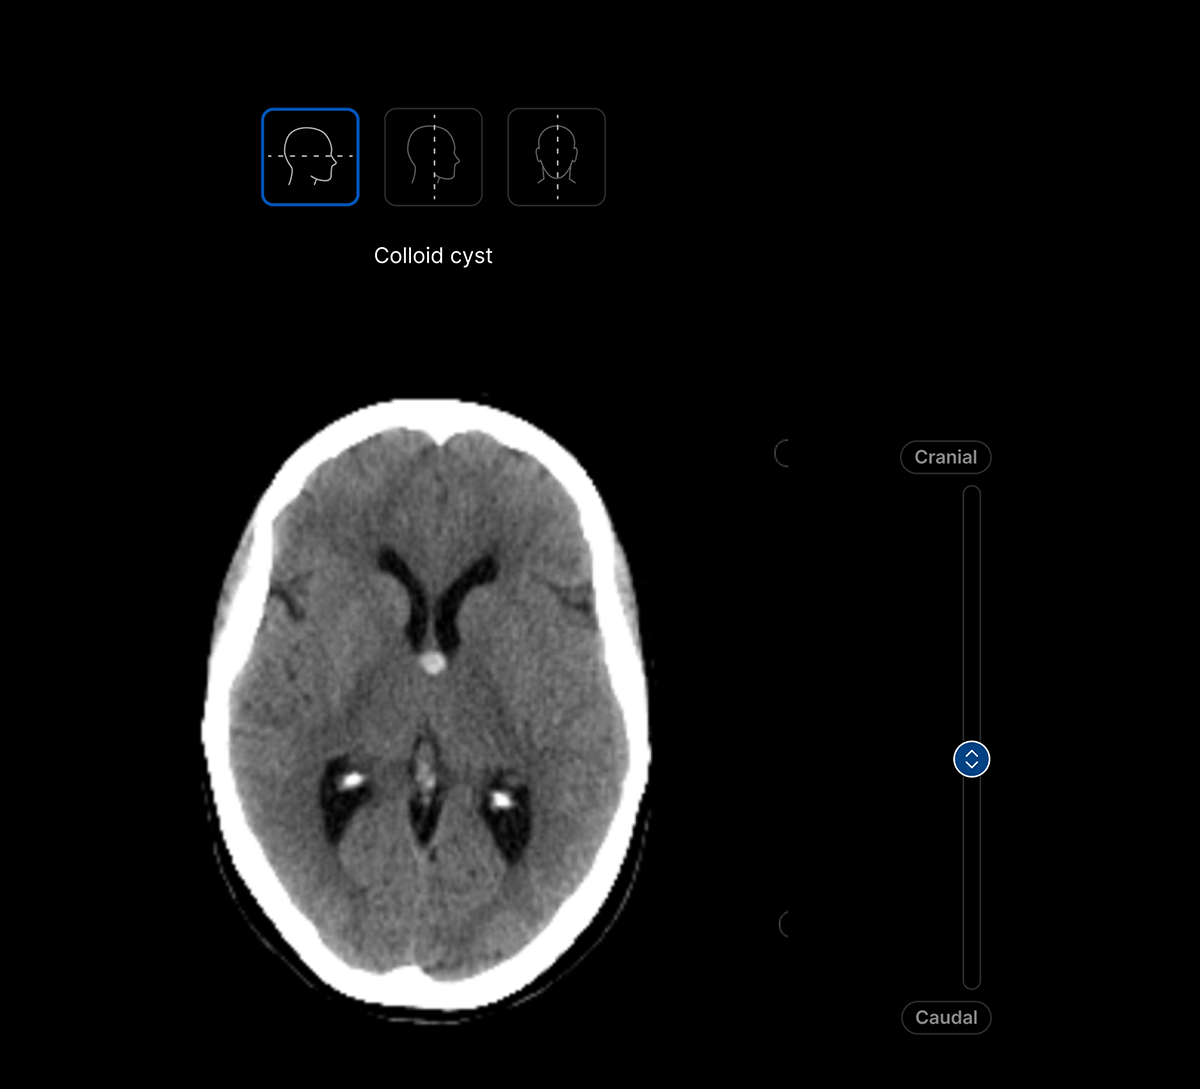

Harrison.ai CT Brain (CTB) is our comprehensive imaging AI solution for non-contrast head CT studies that detects up to 130 findings in under 90 seconds, boosting emergent and incidental capture while surfacing urgent cases for review first – all within the workflow you’re used to.

The UI integrates seamlessly with PACS/ RIS, displaying a resizable, no-click overlay window with findings and localisation.

Maximise clinical value and simplify your workflow with a single comprehensive solution for non-contrast head CT studies, identifying up to 130 findings. No need to juggle multiple solutions for different findings.